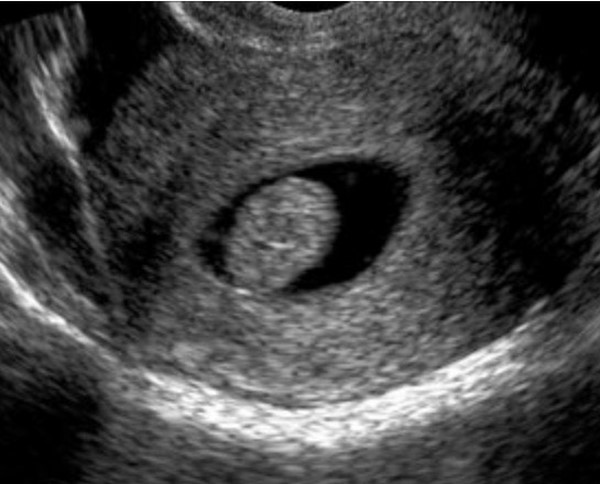

Los avances en este capítulo son extraordinarios. Bien empleados, puede decirse que muy pocas mujeres quedan sin diagnóstico en el caso de presentar patologías. La antigua "laparotomía exploradora" como método para establecer la causa de una enfermedad ginecológica, ha desaparecido en la actualidad. Ya no se concibe operar sin diagnóstico previo. Los avances continuos en el campo de las imágenes, nos permite conocer con creciente precisión, la condición de los órganos genitales pelvianos femeninos. La ecografía es el primer gran auxiliar, indispensable casi, para evaluar el estado anátomofuncional de útero y ovarios por vía abdominal transvesical en mujeres delgadas y sin relaciones sexuales o por vía transvaginal, en aquellas con actividad sexual que aceptan esta vía o en obesas, donde el espesor de la pared abdominal dificulta una buena visualización. En las figuras 1, 2, 3 4, 5 observamos ejemplos de genitales normales y de alguna patología. Hoy día la técnica denominada 4D brinda imágenes excelentes por lo que es empleada con frecuencia en el estudio morfológico del feto en su tercer trimestre.